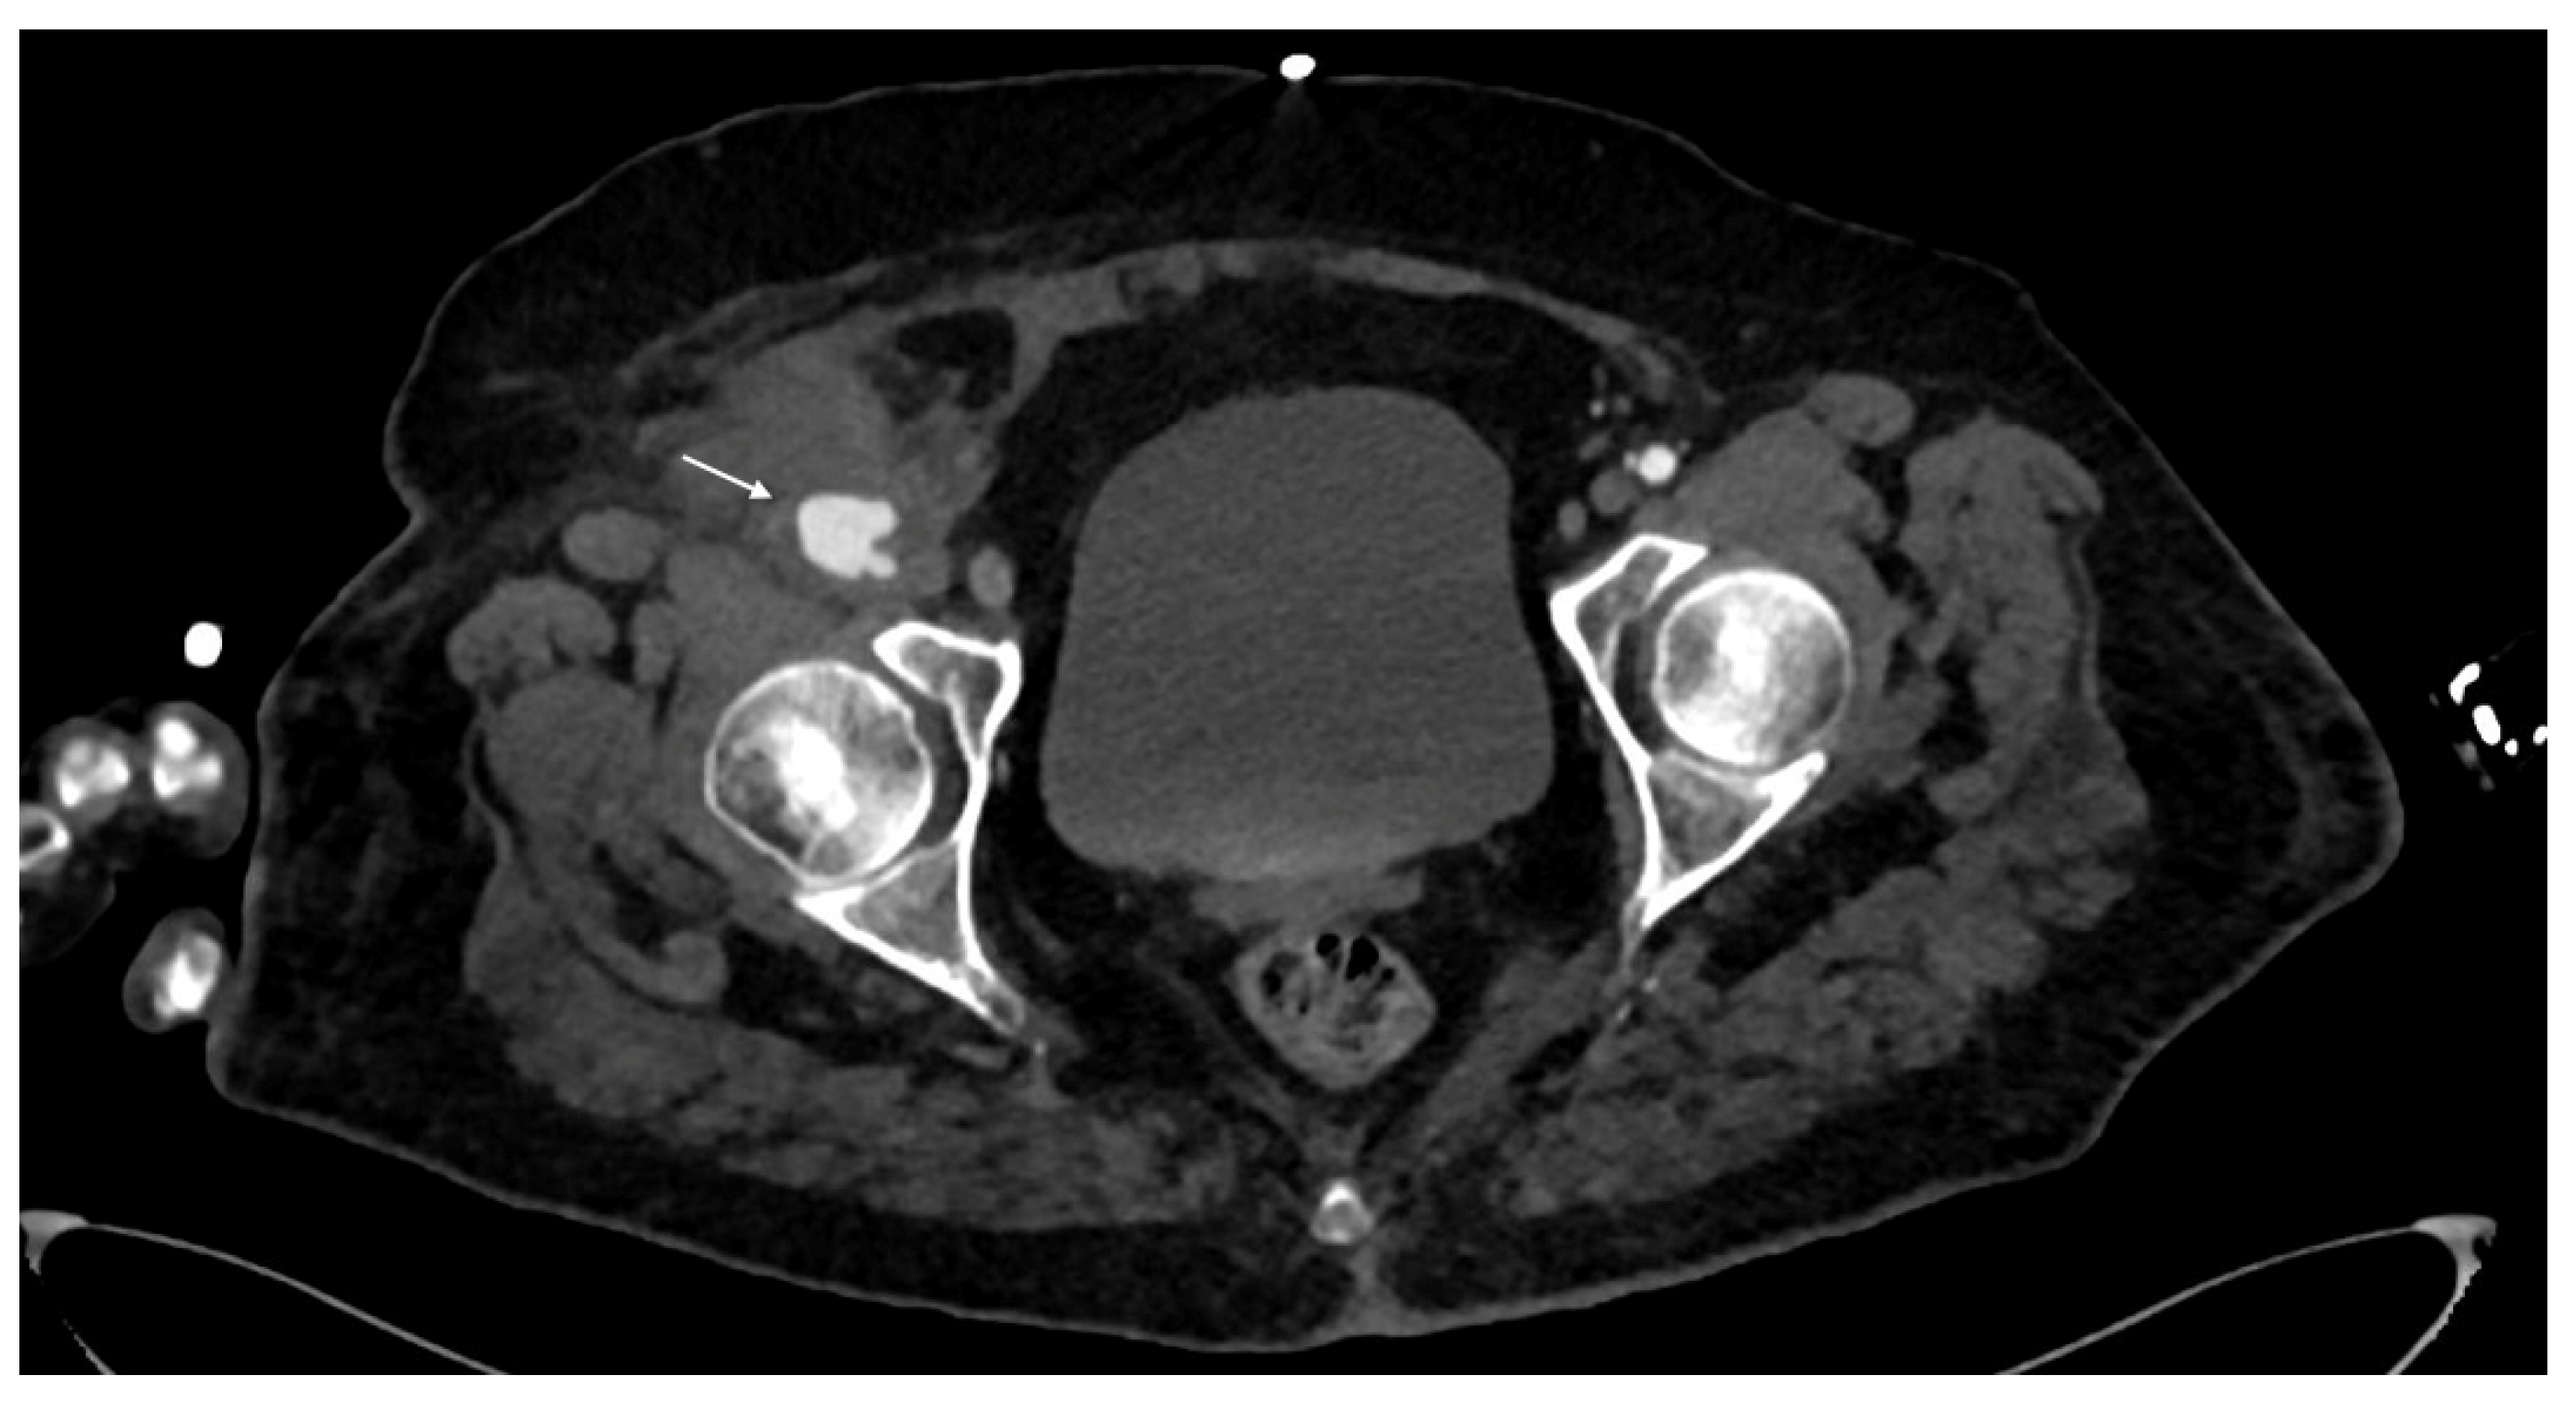

- Pseudoaneurysm is caused by focal arterial wall tear involving intimal and medial layers, and represents a collection of blood contained only by the adventitia layer or surrounding tissue [5,56,59]. It appears as an outpouching sac with a round and smooth margin in continuity with the arterial adjacent lumen (Figure 4). Pseudoaneurysm bleeding appears as irregular, lobulated perilesional contrast blush [65,68]. Pre-exiting calcification or pseudoaneurysm should be differentiate form active bleeding; delayed phase acquisition can be useful because in active bleeding the contrast extravasation dissipates along tissue planes instead pseudoaneurysm and calcification remain stable [60,67].